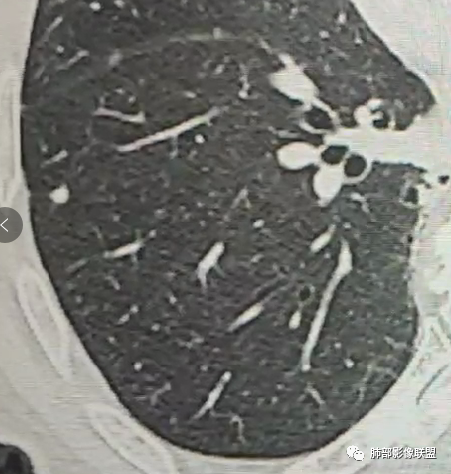

现实工作中万万不能排除转移,但是这几个结节位于左肺下叶背段,周围可见小结节卫星灶,部分胸膜下结节可见胸膜凹陷征,常规考虑原发肿瘤或肉芽肿病变,一个肺区域如此多结节,肉芽肿病变靠前考虑。

左肺下叶胸膜下结节有分叶及胸膜凹陷,边缘似有磨玻璃密度,考虑腺癌。其余结节考虑良性。

2、影像特点:左肺上叶尖后段病灶结合病史考虑消融术后改变,双肺下叶胸膜下可见多发大小不等的实性结节,周围似乎有晕,边缘平直为主,未见深分叶,部分可见邻近胸膜牵拉,张力不高,增强后呈轻中度强化。

10、“葫芦兄弟”:邻近胸膜多发结节,形态接近,排列呈长串状。

(胸膜下多发结节、“蘑菇兄弟”)